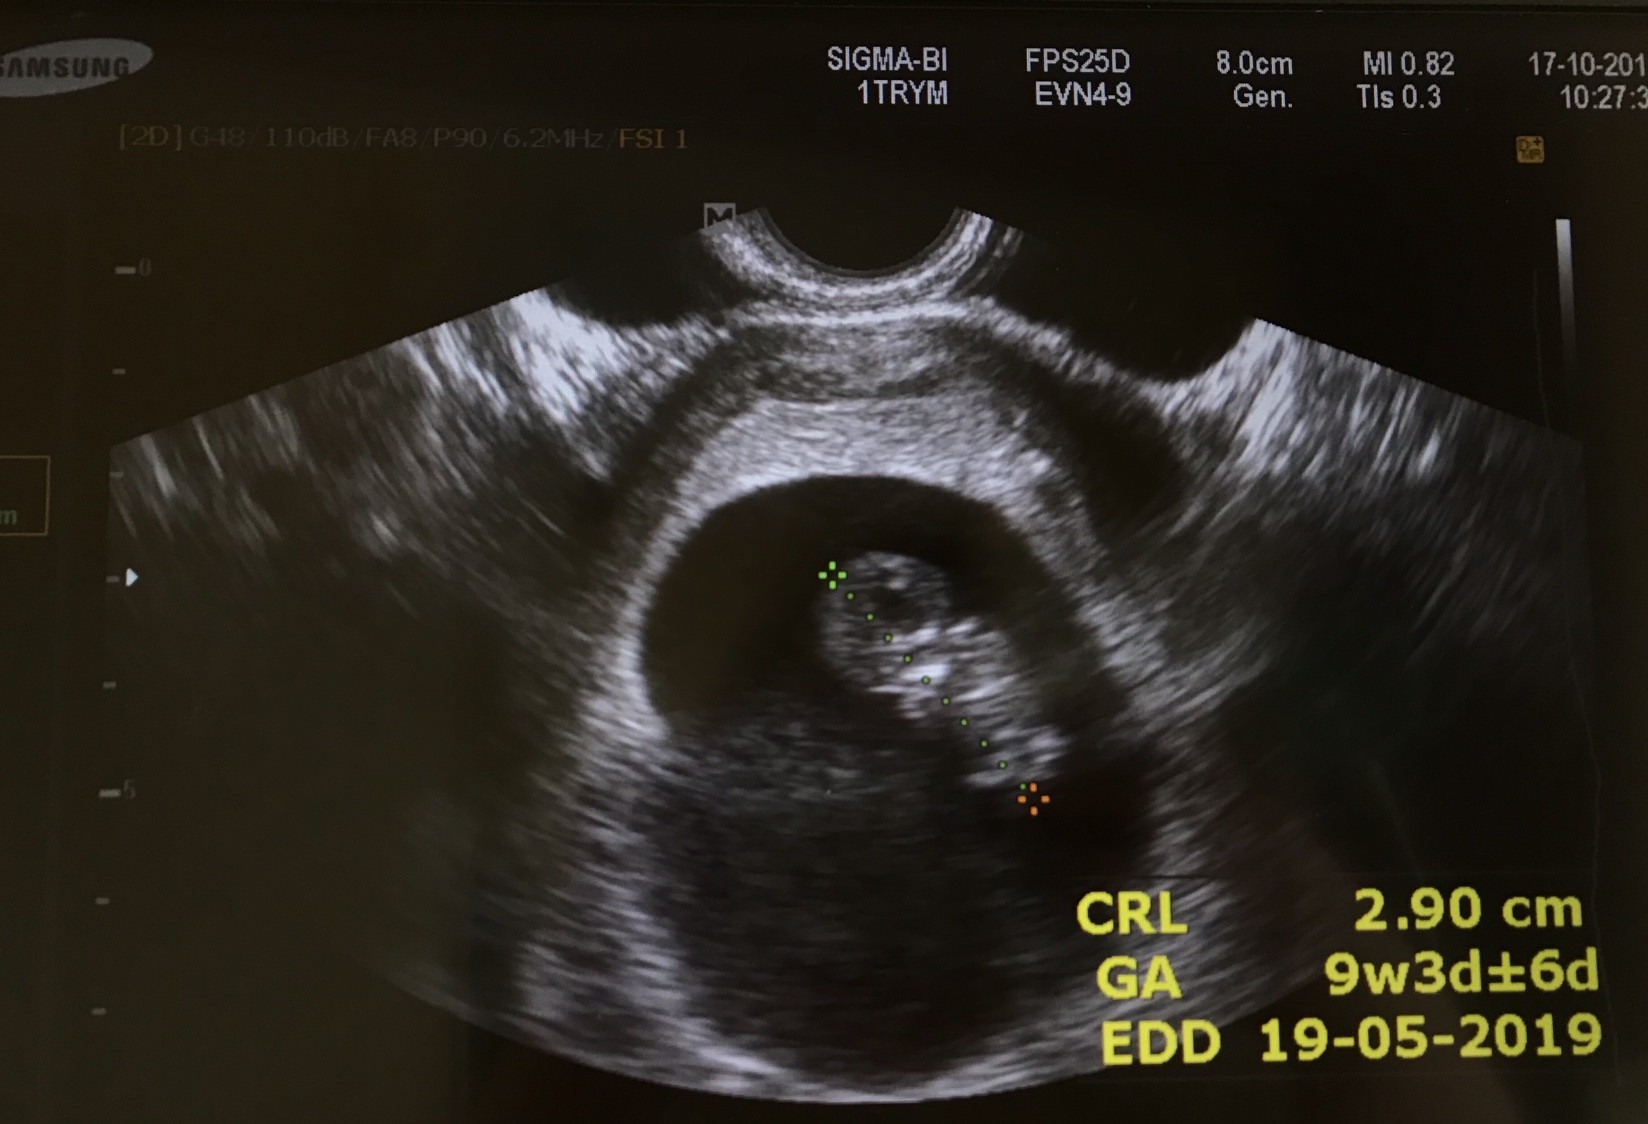

Widziałam pięknie bijące serduszko mojego robaczka, podrzucam wam zdjęcie z dzisiaj :)

Wszystko jest w porządku, wyniki także, dzidzia jest te dwa tygodnie młodsza, bo om miałam 30.07 i to powinien być 12 tydzień, a jest 10. W przychodni wielkie zamieszanie bo im się nie zgadza i nie umiały się doliczyć dwa tygodnie do przodu. Prenatalne mam 30.10, a kolejna wizyta u gin 7.11.

Jaki fajny ludzik, już widać gdzie główka, gdzie nóżki, rączki,